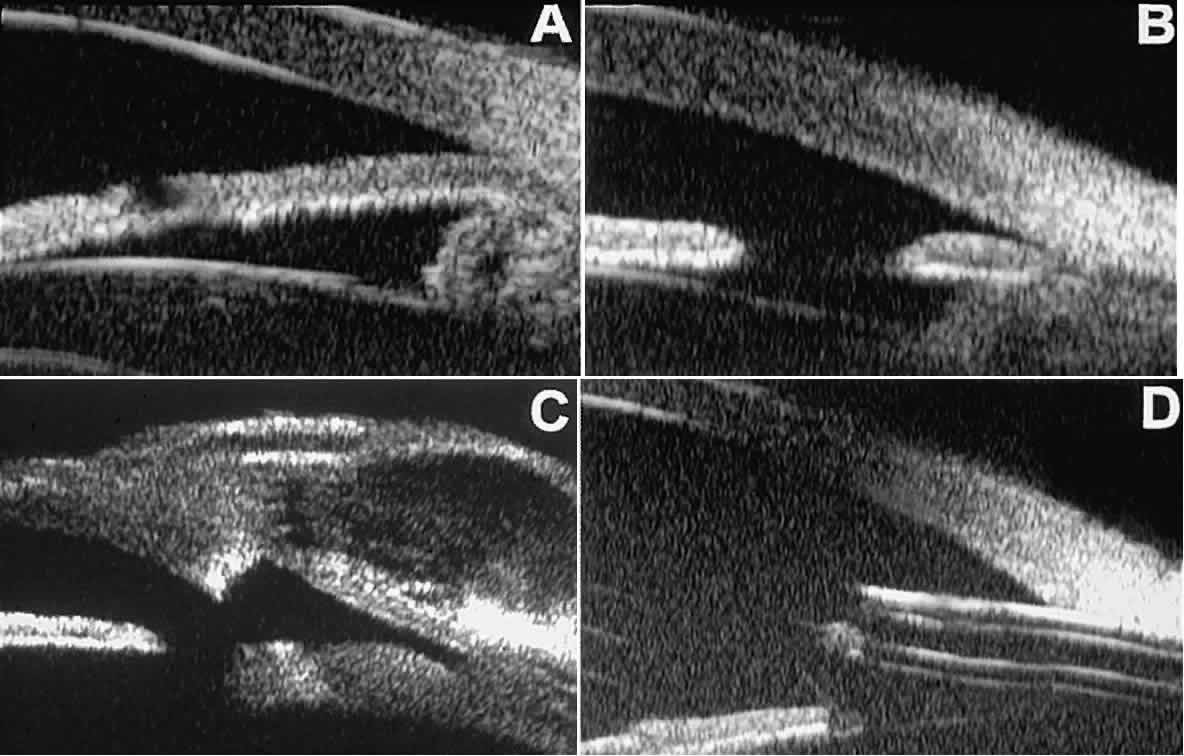

The role of UBM in the preoperative assessment of eyes with cataract is as yet unknown. In certain eyes, however, UBM may reveal features or abnormalities that could alter the ophthalmologist's surgical approach. Postoperatively, UBM can show the size and location of an intraocular lens (IOL) and the positioning of the haptics. A posterior chamber IOL appears on UBM as a highly reflective plate (corresponding to the lens optic) in the retropupillary plane with reverberation artifacts behind it (Fig. 17A). In contrast, an anterior chamber IOL appears on UBM as a sonoreflective plate located anterior to the pupillary plane (see Fig. 17B). In most eyes with a posterior chamber IOL, UBM can show whether the haptics are in the capsular bag (Fig. 18A), in the ciliary sulcus (see Fig. 18B), or in some other anatomic location12 (e.g., resting on the peripheral iris or secured with sutures to the sclera). The haptics are easier to locate if they are made of polymethyl-methacrylate than if they are made of proline because the former has a stronger reflectance.

Fig. 17. Composite UBM images of intraocular lenses. A. Posterior chamber IOL. B. Anterior chamber IOL.

Fig. 18 . Localization of posterior chamber IOL haptics by UBM. A. Haptic in capsular bag (arrow). B. Haptic (bright object just behind peripheral iris) in iridociliary sulcus.

Ultrasound biomicroscopy appears to be helpful postoperatively in determining the extent of postoperative complications of cataract surgery such as serous choroidal detachment (see Fig. 13A), iridocapsular adhesion (Fig. 19A), postoperative hyphema (see Fig. 19B), stripping of Descemet's membrane (see Fig. 19C), and wound gaping (see Fig. 19D).

Fig. 19. Complications of cataract surgery revealed by UBM. A. Capsular adhesion to midzone of iris. B. Postoperative hyphema. Clot appears denser than aqueous with suspended blood cells. C. Stripping of Descemet's membrane. D. Wound gape.